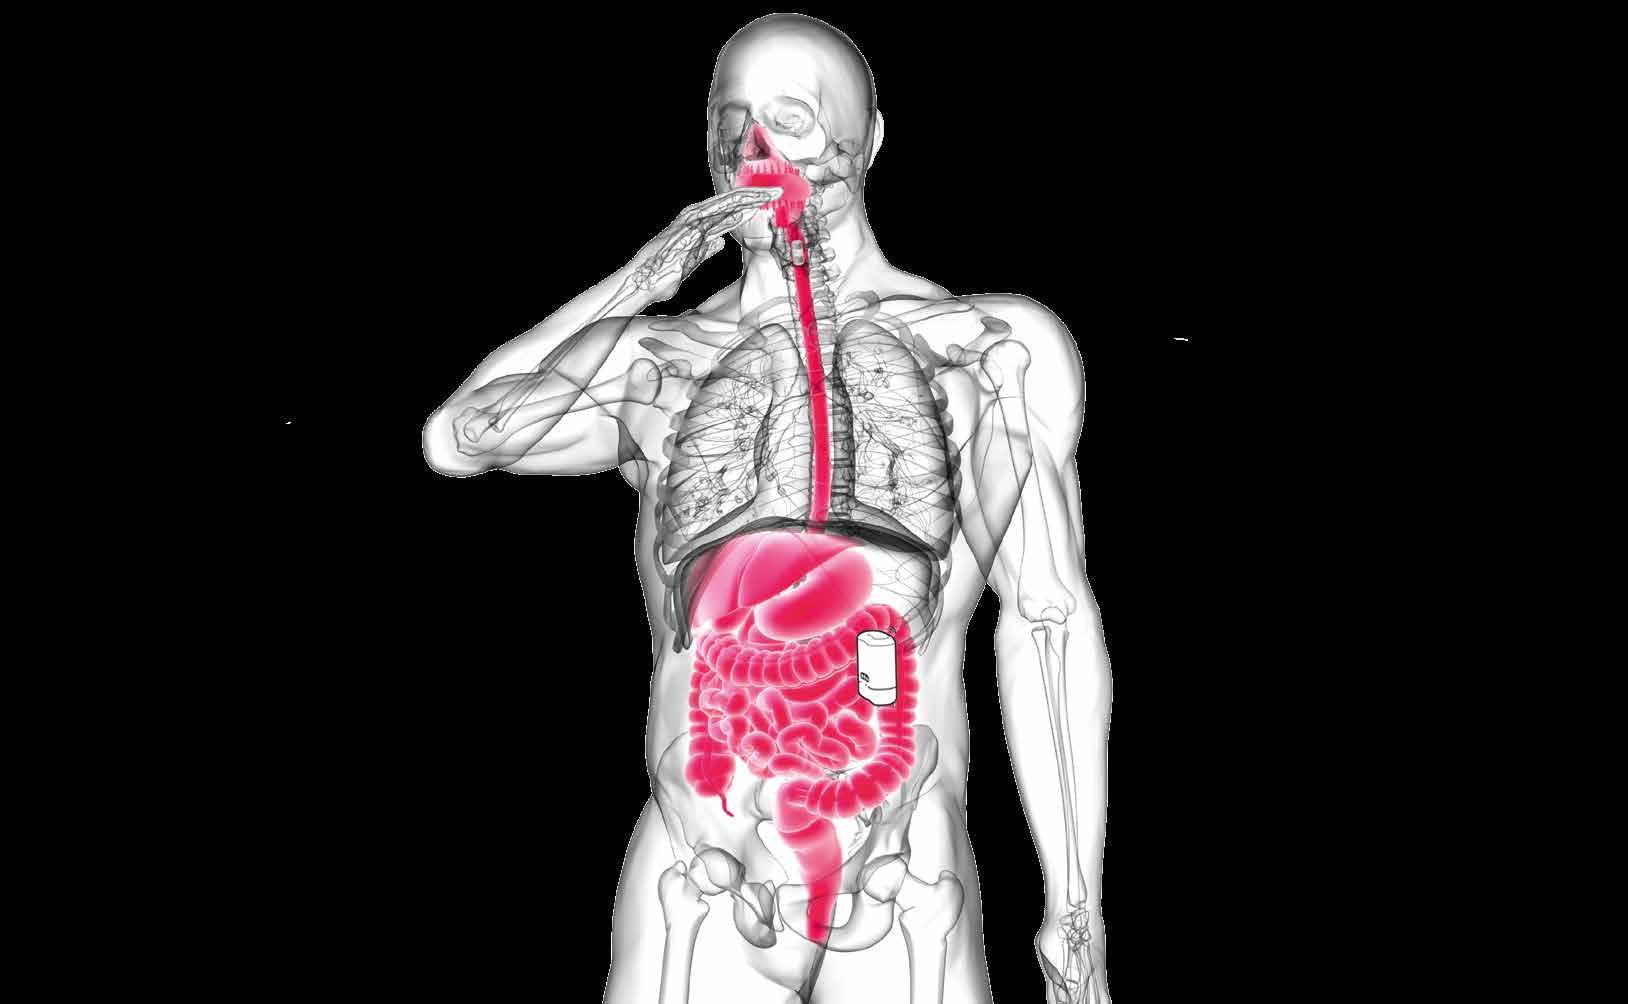

Concept overview of the FORGETDIABETES project.

The device is implanted in the jejeunum, and includes the magnetic system to attract the ingestible capsule and the system to transfer the insulin from (i) the capsule to the reservoir, and from (ii) the reservoir to the body. Electronic components and sensors allow the device to run automaticly, and communicate with the patient.